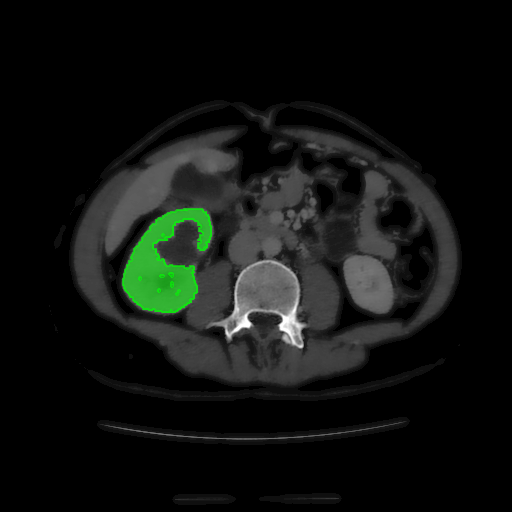

For MSER tracking, Donoser and Bischof [5] presented three different applications; license plate tracking, face tracking and the segmentation of a fiber network. In the third application, a fiber network is reconstructed in 3D by tracking a slice of the data along the axis orthogonal to the image data. Analogously, we track organs in slices of a Computed Tomography (CT) scan, to generate a 3D segmentation. We use the CT data provided in the 3DIRCADb dataset222The dataset is available on http://ircad.fr/research/3d-ircadb-01 [14].

To initialize the tracking process, the organ is segmented in an arbitrary slice of the CT data by a bounding box. The most stable MSHR is then selected in the initialization process for tracking. The respective MSHR is tracked through the slice data along the axis orthogonal to the image data. An example of the tracked regions is visualized for two examples in Fig. 7. Given the segmentations of the single slices, the organ can be reconstructed in 3D. We compare the reconstruction for MSER and MSHR tracking in Fig. 8. To enhance the visualization, the datapoints are triangulated and the surface normals calculated. Since the contrast of the organs can be very low in CT images, the MSER tracking has difficulties catching the organ boundaries. Furthermore, the organ is sometimes partely lighter and darker than the background, which may lead to MSER tracking failure. The proposed MSHR tracking copes well with these difficulties, and the reconstructions are significantly better.

Figure 7: Two examples sequences from the 3DIRCADb dataset [14]. Given an initial selection of a single slice (the middle image in (a) and (b)) of the organ, the proposed MSHR tracking tracks the region forward and backwards in space. The segmented slices can be used to reconstruct the organ, see Fig. 8 for an example reconstruction.